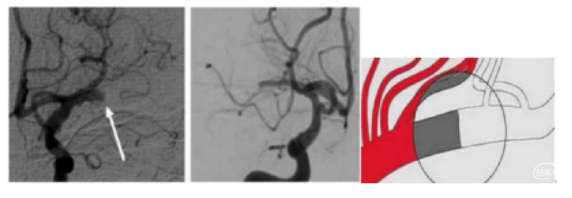

三、血管开窗

血管开窗变异畸形常见于大脑中动脉、基底动脉、椎动脉 V3 段。血管开窗(犹如水流绕行孤岛)在取栓中很容易被误认为是血管狭窄,由于开窗两侧的血管往往非常细小,一旦行球囊扩张,很容易出现血管破裂的灾难性后果。

术中注意对此类病因病变的判定,避免并发症发生。下图:大脑中动脉 M1 段血管开窗畸形。